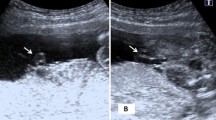

Eighty to 85% of the venous perfusion to the fetal liver is from the umbilical vein, the rest from the portal vein. Umbilical venous flow to the liver is essential for intrauterine growth, and is impaired in placental insufficiency. We hypothesized that in growth-restricted fetuses portal blood flow compensates for insufficient umbilical blood flow to the liver. In 29 fetuses with fetal growth restriction (estimated fetal weight ≤5th percentile), we used ultrasound to measure blood flows in the umbilical vein, ductus venosus, left portal vein, and main portal stem. Compared with normal fetuses, both absolute and normalized total venous liver blood flows were reduced in growth-restricted fetuses, related to the degree of placental compromise and equally affecting both liver lobes. However, portal replaced umbilical flow to the right lobe, in a manner graded according to placental vascular resistance; in extreme cases, the right lobe received no umbilical perfusion. In fetal growth restriction, the liver suffers from venous hypoperfusion, and portal blood partially replaces umbilical flow to the right lobe; this will result in right liver lobe hypoxemia. This striking prioritization in nutrient delivery of left over right lobes suggests an adaptive response to poor placental perfusion that may have functional consequences.